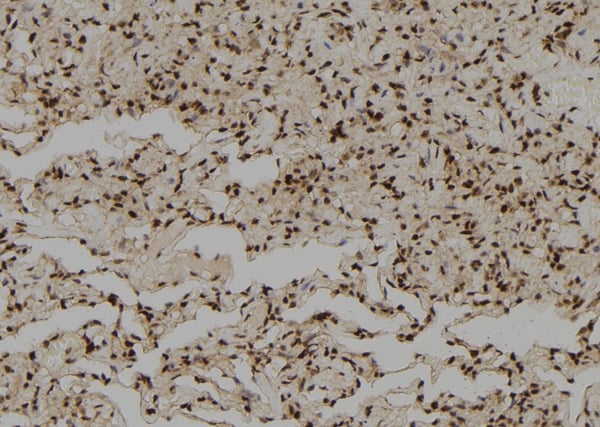

IHC (Immunohistochemisry)

(At 1/100 staining human lung cancer tissue sections by IHC-P. The tissue was formaldehyde fixed and a heat mediated antigen retrieval step in citrate buffer was performed. The tissue was then blocked and incubated with the antibody for 1.5 hours at 22 degree C. An HRP conjugated goat anti-rabbit antibody was used as the secondary)